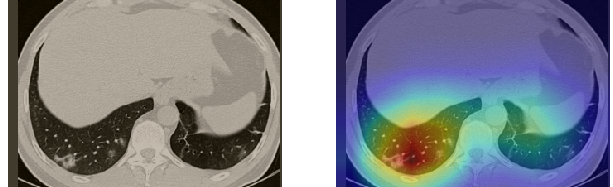

In order to make our models more transparent and provide detailed visual analysis, we present the Grad-CAM localization maps obtained by different models. We consider CT images with COVID-19 abnormalities from the test set of each dataset and highlight the important regions considered for the prediction. For the SARS-CoV-2 dataset we use the Inception V3 model. Figure 13 shows the original CT images and their localization maps. Our model is capable to detect regions that show abnormalities in the CT scans.

In a similar way, we consider classifying the test CT scans from the COVID-19 dataset by the DenseNet169 model and highlight the important regions considered for predictions. We present the original CT images and their localization maps in Figure 13. We can also see that our model is capable to detect the COVID-19 related regions as marked (small square in some images) by expert radiologists.

A wide variety of typical and atypical CT abnormalities have been reported for COVID-19 patients in various studies [58, 59]. So, we tested our models on external CT images extracted from these two publications as they feature typical findings of COVID-19 pneumonia marked by specialists. In order to make sure that not any of the extracted images are unintentionally included in our datasets, specifically the COVID19-CT dataset, we use the model trained on the SARS-CoV-2 dataset. First, the InceptionV3 model is employed to classify the extracted CT images. The model is able to correctly classify the given CT images as COVID-19. Second, in order to interpret the model’s generalization capabilities, we apply the Grad-CAM technique to visualize the regions of abnormalities that are considered. By assessing the different CT images in Figure 15, we can see that the model accurately localizes the disease-related regions. Even more interesting is the fact that the model ignores any specific marks in the images like letters and only localizes the COVID-19 related regions. These visual explanations show the success of our models to learn relevant, generic visual features related to COVID-19 and are capable to correctly classify CT images outside the datasets on which they are trained.